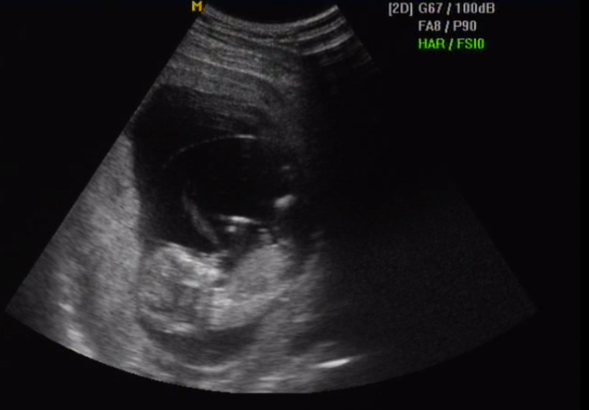

Hát nem tudom, az uhus nő ámult csak, hogy na ez a gyerek idősebb már, 3 nap lett végül az eltolódás. Az igazság az, hogy fogalmam sincs mikor keletkezett…lehet a számolás szerinti mai kor 16+1, és igen, max 3 nappal is lehet idősebb. És kettővel is…ezeken a napokon tuti adtunk neki esélyt.

De mivel a kis kukacok eléggé túlélőek, így 1 nappal is lehet idősebb, amikor is nem volt konkrét akció…és az igazat megvallva én ezt tartom a legvalószínűbbenek…nem tudom miért. Na végülis tökmindegy, úgysem a kiírt dátumon fog jönni, akár hány naposnak számolom…csak a vonalzó miatt érdekelne a dolog, hogy most akkor hogy vegyek a számokat.

Ja és asszem most kicserélem a vonalzómat arra a korra, amit legutóbb állapítottak meg….aztán majd látjuk a következő uhu után….bár akkor már sztem napra pontosan tuti nem tudják megmondani. (19+2-n megyek)